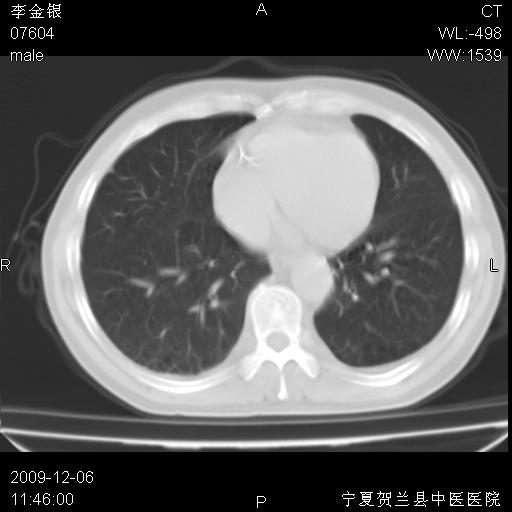

该病人 ,男,62岁,主因咳痰带血两天

考虑右肺中央型占位性病变并阻塞性肺炎.(右肺上叶支气管变窄),建议支纤镜检查.

考虑右肺中心型肺癌伴阻塞性肺炎及右肺门淋巴结转移,建议纤维支气管镜进一步检查。

支气管壁明显增厚 管腔狭窄,腔静脉后多个淋巴肿大,结合年龄病史考虑右肺上叶中央型肺癌并阻塞性肺炎

右肺上叶后段支气管阻塞,右上肺门占位,相应肺段阻塞性肺炎,右肺门有淋巴结肿大。诊断右肺上叶中心型肺癌,阻塞性肺肺炎、右肺门淋巴结转移。

右上叶支气管狭窄,管壁增厚,远端斑片状软组织影,病灶邻近叶间裂,叶间裂无移位。

诊断右肺中央型肺癌。

那个片影应该大部分都是病灶,病灶沿肺段支气管分支生长,后段完全显示不清、闭塞。若为不张应该伴有叶裂的移位,若为炎症应有空气支气管征。

右肺中心型肺癌伴阻塞性肺炎及右肺门与纵膈淋巴结转移很典型,可纤维支气管镜进一步检查

考虑右侧中央型肺癌伴右肺上叶后段阻塞性炎症、肺不张、右肺门和纵隔淋巴结肿大。

右肺上叶中心型肺癌,阻塞性肺炎、右肺门和纵隔淋巴结转移。